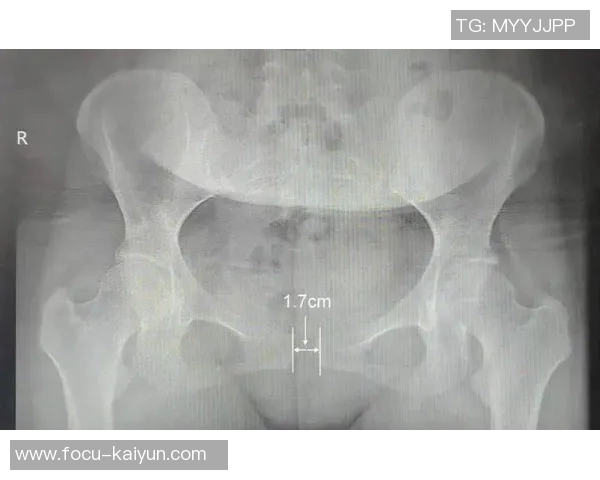

“耻骨痛”是指耻骨联合部位的疼痛,这种症状常见于足球、篮球等高强度运动项目中,特别是涉及快速跑动、急停急转的运动员。亚马尔的情况也并非个例,很多职业球员在高强度的竞技中常常忽视小伤,导致类似的困扰。

耻骨痛通常由过度使用、肌肉不平衡或外部冲击等因素引起。在高强度的足球比赛中,快速的方向变化、频繁的启动和停止,这些都会对耻骨联合产生极大的压力。尤其是当运动员在场上过度使用某些肌肉群,导致身体不均衡时,耻骨联合的软骨和韧带就容易受到损伤,进而引发疼痛。

对职业运动员而言,耻骨痛不仅仅是一种痛感,更是对他们竞技状态的致命打击。医生强调,耻骨痛的最大隐患在于它的隐蔽性和慢性化。当疼痛逐渐积累并未得到及时的治疗时,可能会造成肌肉、韧带的长期损伤,甚至影响骨盆和髋部的稳定性,导致更加严重的运动损伤。